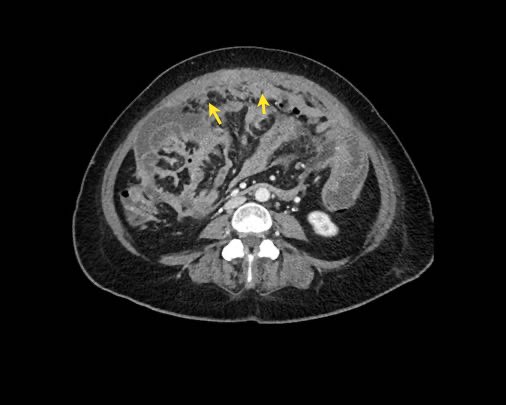

Hình ảnh

Hình ảnh CT của một bệnh nhân ung thư phúc mạc.

Một lượng nhỏ dịch cổ trướng hiện diện ở góc phần tư trước bên phải.

Các đường dày dạng nốt vuông góc với thành ruột được ghi nhận.

Hình ảnh này đại diện cho tổn thương xâm lấn mạc treo ruột lan rộng (mũi tên).